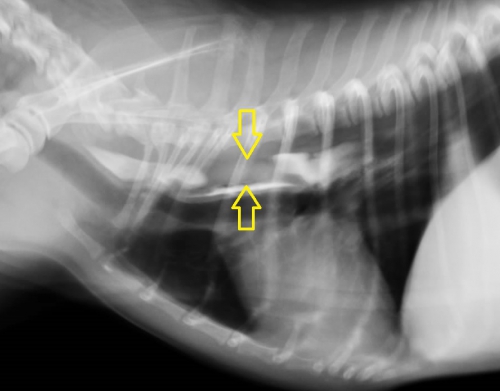

こういった場合、まず、レントゲン検査を行って異物の見当をつけます。下の胸部レントゲン写真で黄色い矢印に挟まれた部分が少し白っぽく見えるのがお分かりでしょうか?実は画像診断ではこういった特徴ですぐに胸部食道の異物を疑うことができます。

下の写真が食道バリウム造影検査を行って確定診断を行った写真です。同じ部位に造影剤によって明らかになった形のはっきりしない異物が造影されています。

リンゴ程度のカタマリがいかにレントゲン写真に映り難いのかがお分かりになりますでしょうか?